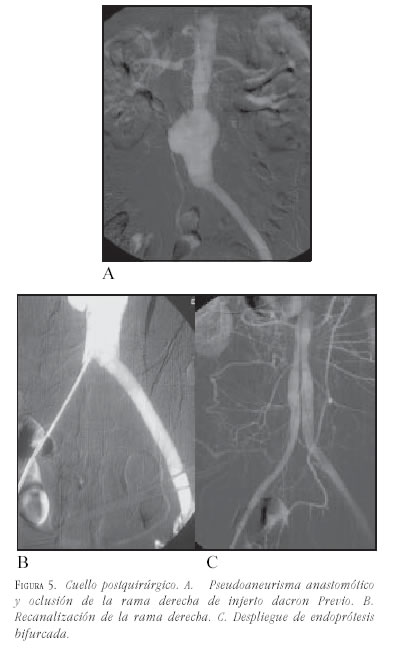

- Posquirúrgico: las dilataciones que se producen entre las arterias renales y una prótesis ya implantada quirúrgicamente en general no tienen cuello, lo cual sería una limitación; pero el sólo recubrimiento de la pared impide que el flujo choque directamente sobre la pared arterial y sí sobre el injerto, hace esto que sea una indicación para evitar la progresión del segmento dilatado (figura 5).

- Dobles: las limitaciones producidas por cuellos que pueden ser definidos como dobles, están referidas a las posibilidades de sellar el segundo cuello, siempre considerando que el segmento dilatado entre los dos cuellos debería estar recubierto por la prótesis, es decir, el diámetro que se elija debería ser como mínimo el diámetro del segmento indicado.